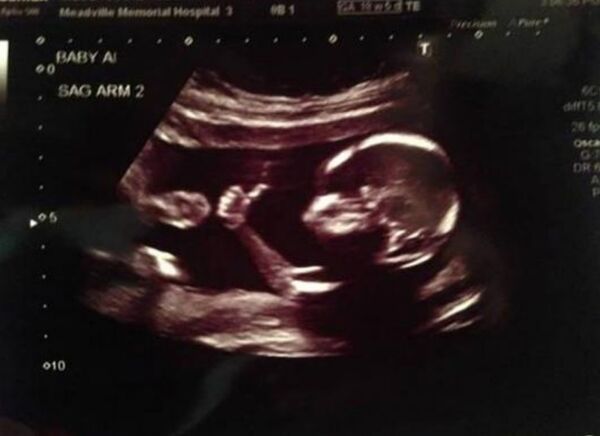

Bebekler anne karnında ne yapar?